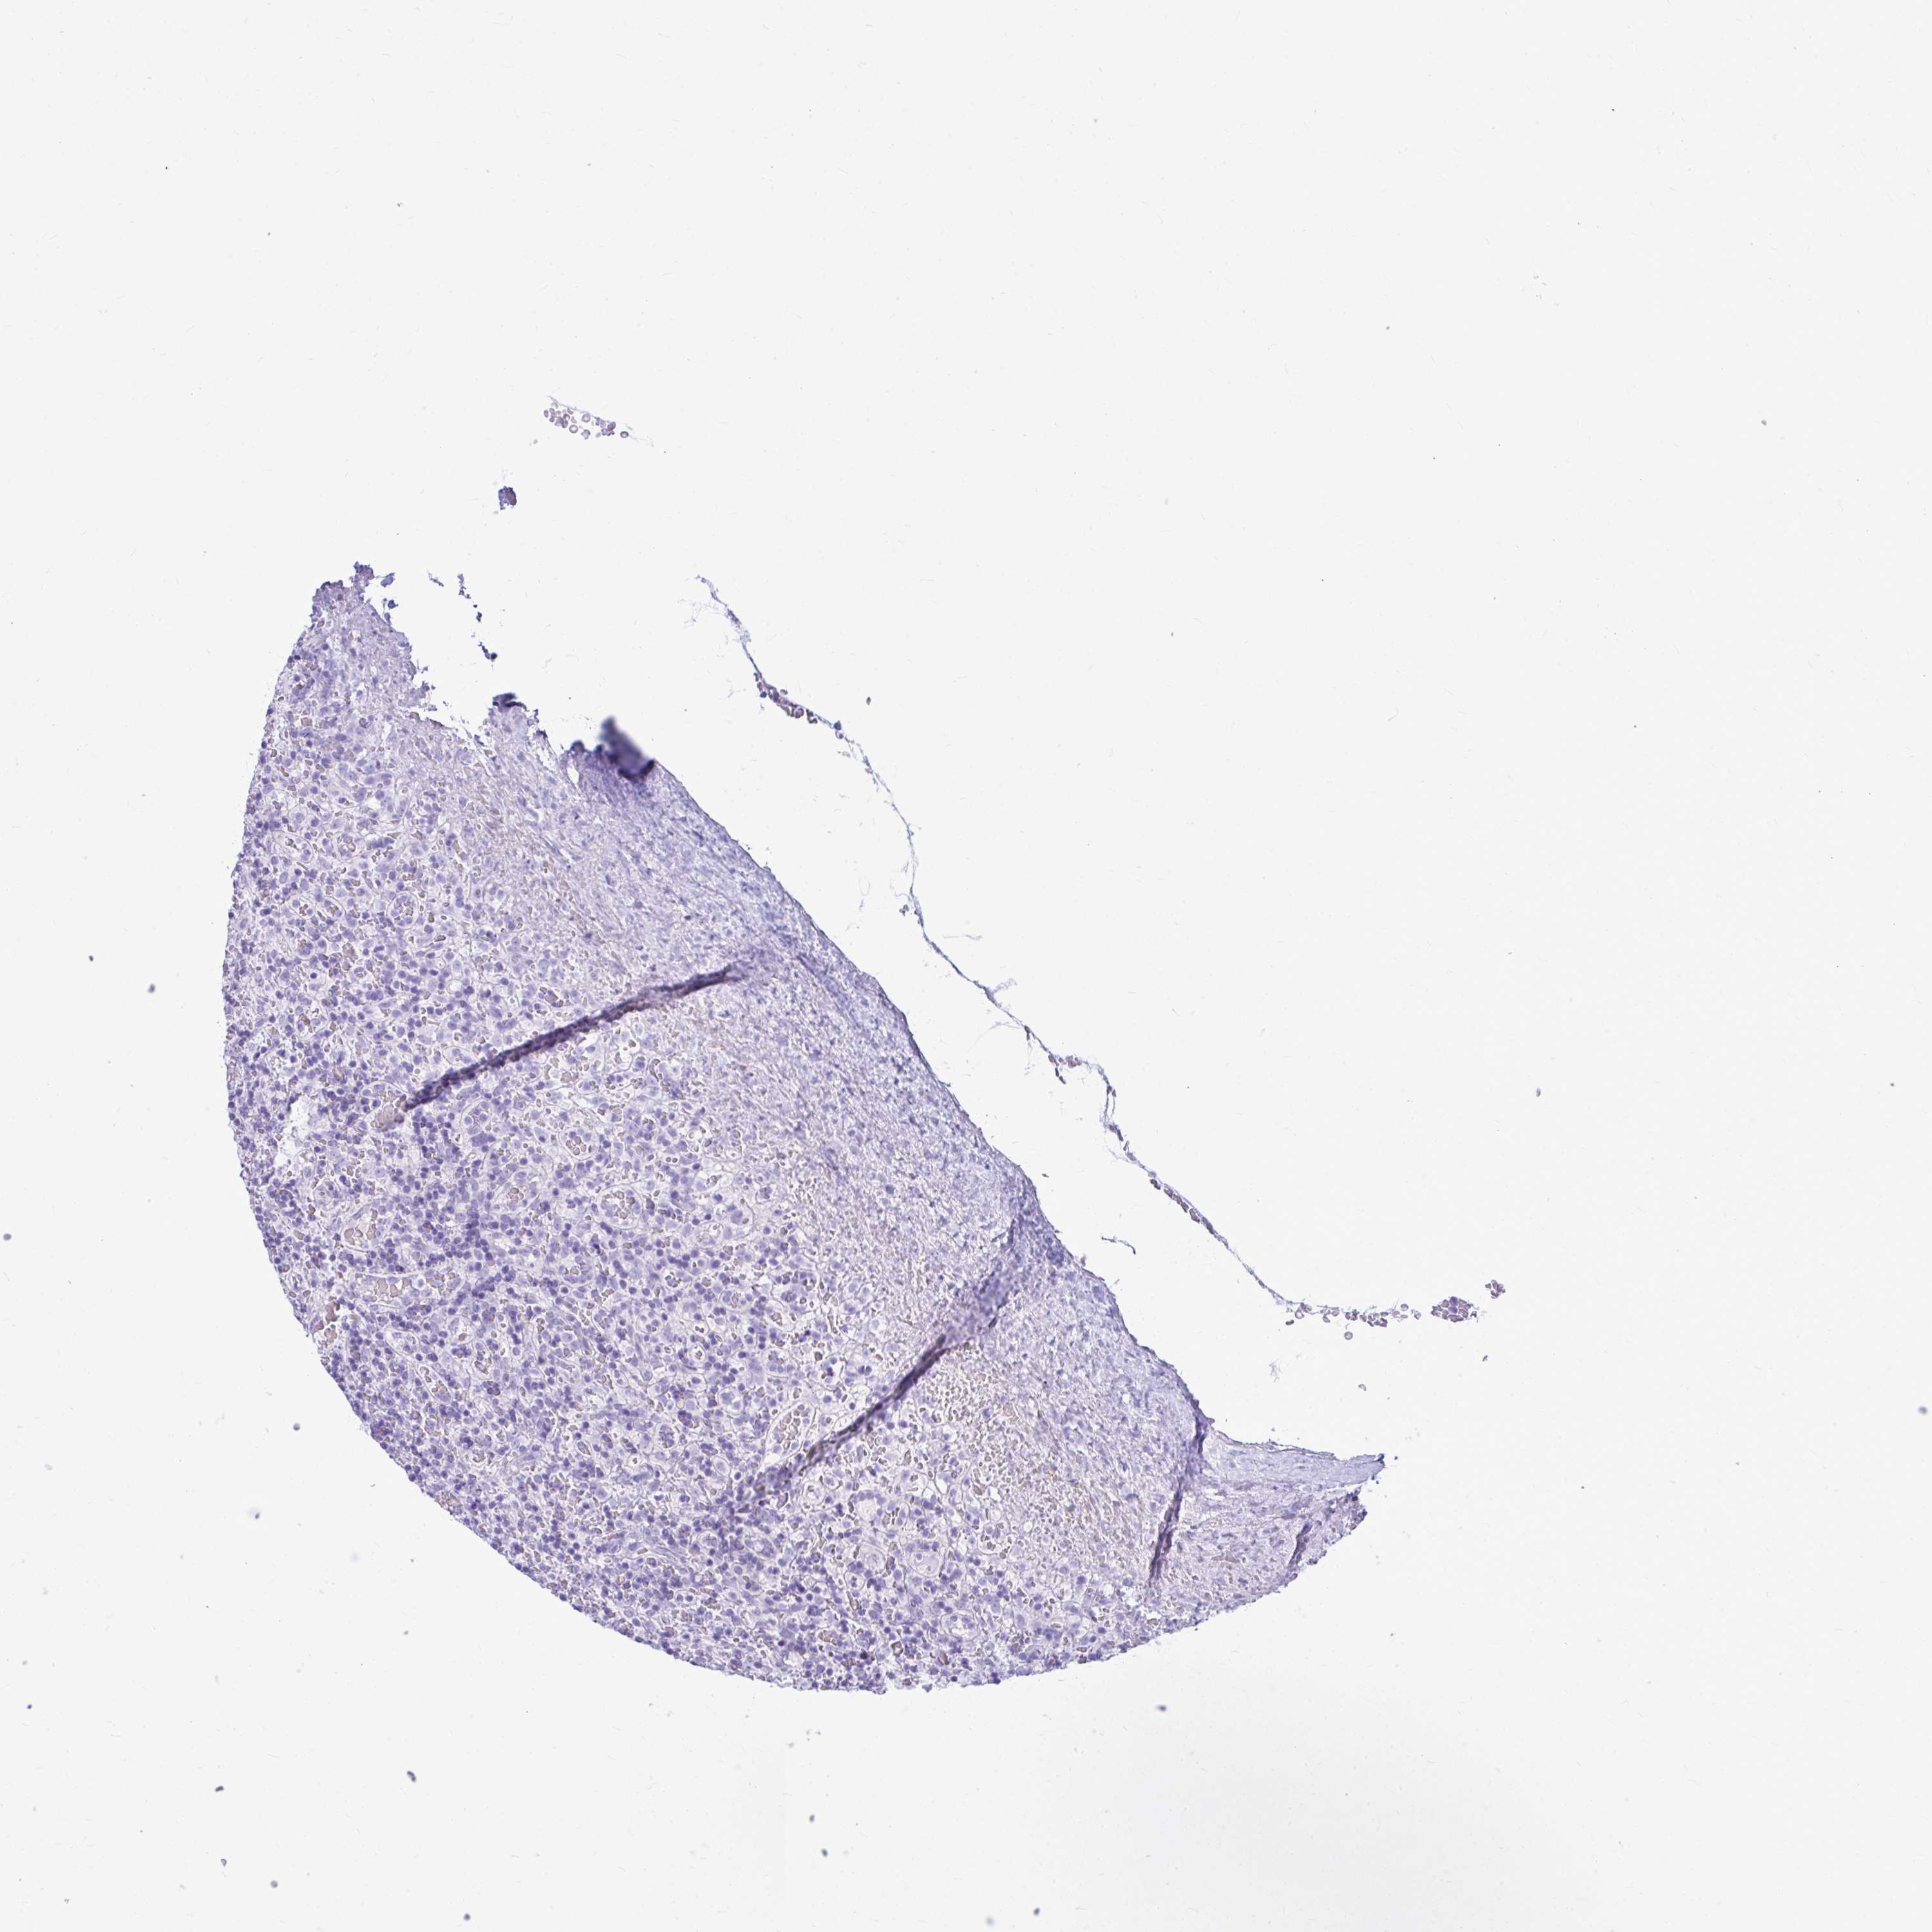

CANCER LYMPHOMA Show tissue menu

LYMPHOMA - Protein expressioni

A mouse-over function shows sample information and annotation data. Click on an image to view it in a full screen mode. Samples can be filtered based on level of antibody staining by selecting one or several of the following categories: high, medium, low and not detected. The assay and annotation is described here.

Each image is clickable and will lead to virtual microscopy that enables deeper exploration of all samples and also displays staining intensity scores, fraction scores and subcellular localization as well as patient and tissue information for each sample.

Antibody HPA048761

Antibody HPA058627

Antibody CAB020709

Malignant lymphoma, non-Hodgkin's type, Low grade

Malignant lymphoma, non-Hodgkin's type, High grade

Hodgkin's disease, NOS